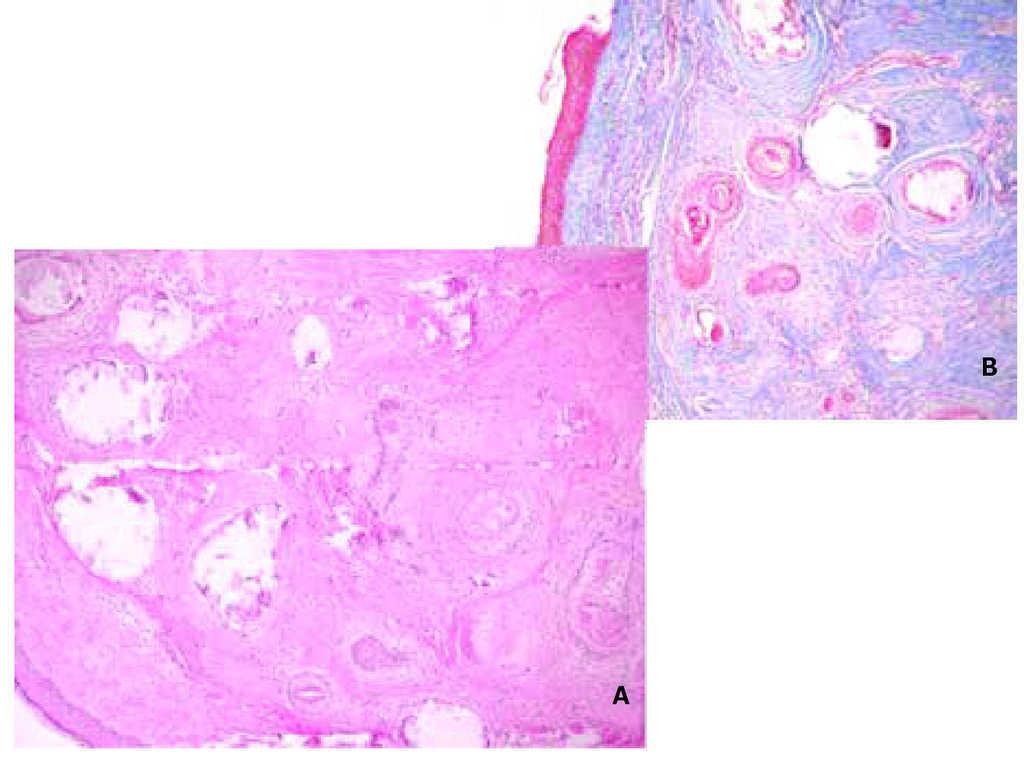

El estudio histopatológico fue reportado como proliferación celular que afectaba sólo a la dermis, constituida por múltiples folículos pilosos y cavidades quísticas junto con un abundante estroma fibroso y escasa reacción inflamatoria (Figura 2).

Figura 2. Corte histopatológico de la lesión. A) Tinción hematoxilina & eosina. B) Tricrómico de Masson.

Las lesiones solitarias consisten en pápulas o nódulos bien circunscritos, que pueden simular carcinomas basocelulares, nevos nevocelulares u otras lesiones benignas. Histológicamente, encontramos una proliferación celular intradérmica dentro de un estroma denso e importante con poca reacción inflamatoria acompañante, junto a la presencia de cuerpos córneos que pueden sufrir calcificación distrófica e islas de células basaloides,5 en ausencia de figuras mitóticas.